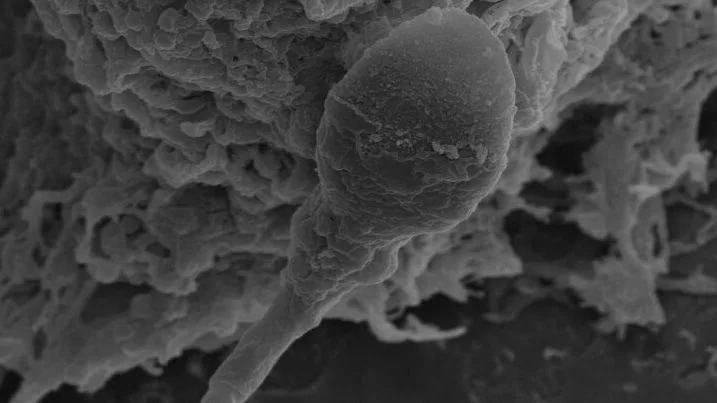

Can humans have babies in space? It may be harder than expected

When you buy through links on our articles, Future and its syndication partners may earn a commission. Humankind is bound to become a space-faring species, expanding beyond the bounds of Mother Earth, just as it, millions of years ago, spread out of its cradle in Africa. At least that's what space exploration leaders such as the world's richest man Elon Musk would like you to believe. However, there may be biological hurdles that could forever confine this vision to the realm of science fiction and human civilization to our Earthly soil. A new study found that sperm cells of mammalian species including humans, mice and pigs struggle to find their way through a female reproductive tract in microgravity to reach and fertilize an egg. Even when the sperm makes it to its destination, the study found that embryos formed in these conditions develop poorly compared to those evolving in normal gravity. The study, from researchers at the University of Adelaide in Australia, is just the latest addition to a growing pile of evidence that suggests mammalian reproduction in space might be quite complicated, if not impossible. There have been some previous studies with headlines stating mouse babies were born from stem cells subjected to months-long spaceflight, but most earlier research, conducted either in space or in microgravity simulators on Earth, has revealed a plethora of negative effects the space environment has on reproductive cells and embryos. "When you think about the future of space exploration and space settlements, it's happening. It's happening now," Nicole McPherson, a reproductive biologist at the University of Adelaide, Australia, and lead author of the paper, told Space.com. "I think people forget that for us to maintain these settlements without having to continually colonize them from Earth, we need to be able to reproduce in space." McPherson, whose previous work covered the effects of obesity and diet on the success of conception, got intrigued by the question of the possibility of in-space reproduction after watching a documentary hosted by British physicist Brian Cox. A discussion with her partner then spawned an idea for a unique research experiment. A chance encounter with the founder of space medicine company Firefly Biotech a week later allowed her to acquire a 3D clinostat for her lab. This device is a high-tech centrifuge that simulates microgravity by spinning vials with samples around two axes, effectively confusing the cells inside as to their position in space. In her experiment, McPherson and colleagues created a set-up holding human, mice and pig sperm cells in one part of the compartment and egg cells in the other, divided by a thin channel simulating the female reproductive tract. The researchers observed that 30% fewer sperms were able to make it to the egg compared to those in normal gravity. Scientists know sperm relies on a complex set of signals to find its way to an egg. Part of that navigation is driven by chemical cues, such as concentrations of the female hormone progesterone, but gravity seems to play a significant role too, McPherson said. "We know that sperm responds to chemical cues, but we also know that they like to swim near surfaces," she said. "Obviously, to know where surfaces are, you need to understand your position in time and for that you need gravity." The struggle of sperm to make it to the egg was only one part of the findings. When sperms managed to reach the eggs, the ensuing early-stage embryos, called blastocysts, initially appeared stronger than their counterparts conceived in gravity. However, when microgravity exposure continued, the superior quality of microgravity-conceived blastocysts deteriorated and the embryos started to lag behind their normal counterparts. McPherson thinks the initial quality gain observed in embryos formed after only four hours of microgravity exposure was due to the natural selection process that had occurred, allowing only the fittest sperms to reach the eggs. The subsequent deterioration in embryos that had been in microgravity for up to 24 hours was likely due to negative effects the absence of gravity has on the processes taking place in the quickly dividing embryonic cells. "There are so many changes that happen in those first 24 hours of embryo development," McPherson said. "You have the maternal and the paternal DNA coming together. You have lots of epigenetic remodeling that goes on to drive early foetal development. And that being exposed to zero gravity is actually really detrimental." McPherson said the researchers would, in the future, want to conduct similar experiments in reduced gravity, such as that of the moon or Mars, to see whether partial gravity might mitigate the problem. She thinks the findings have implications not just for the visions of space settlements, but also for commercial space tourism and babies potentially conceived on lunar and orbital honeymoons. The natural selection leading to the formation of stronger embryos after short microgravity exposures, on the other hand, could lead to advances in human IVF technologies that help treat infertility on Earth. In the future, the researchers would like to expose the embryos to longer microgravity spells to gain deeper insights into the processes taking place in space-like conditions. The study was published in the journal Communications Biology on Thursday (March 26).